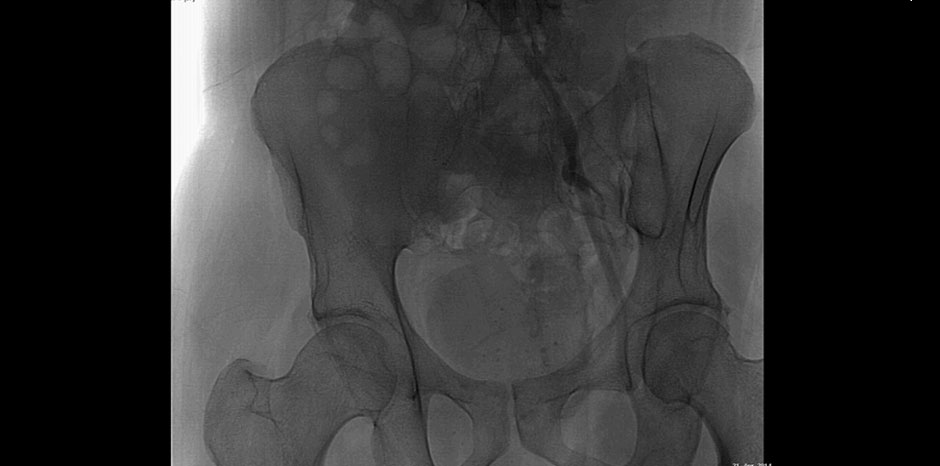

• PRE-OP ANGIO

• RIGHT ILIAC STENT OCCLUDED

• Angiography : B/L Iliac artery stenosis ( R-80%, L-50%) with B/L SFA occlusion distal to adductor canal extending onto popliteal artery

• B/l Iliac artery stenting with left femoro-popliteal bypass done in March 2013

• Now presented with rest pain and non healing ulcer over right leg amputation stump since Jan 2014